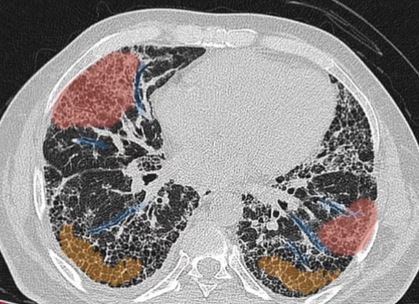

폐 섬유증은 폐에 염증이 반복되면서 정상적인 폐 조직이 점차 흉터 조직(섬유조직)으로 바뀌는 질환입니다. 이 섬유조직은 고무처럼 탄력이 없고 단단해, 한 번 형성되면 정상 폐로 되돌아가지 않는다는 특징이 있습니다. 이로 인해 폐가 충분히 팽창하지 못하고, 산소를 받아들이는 능력이 점점 떨어지게 됩니다.

이러한 변화 때문에 폐 섬유증은 단순 염증성 질환인 폐렴이나 기관지염과 달리, 진행성·비가역적인 폐 질환으로 분류됩니다.

✔ 흉부 CT에서 이상 소견이 나온 경우